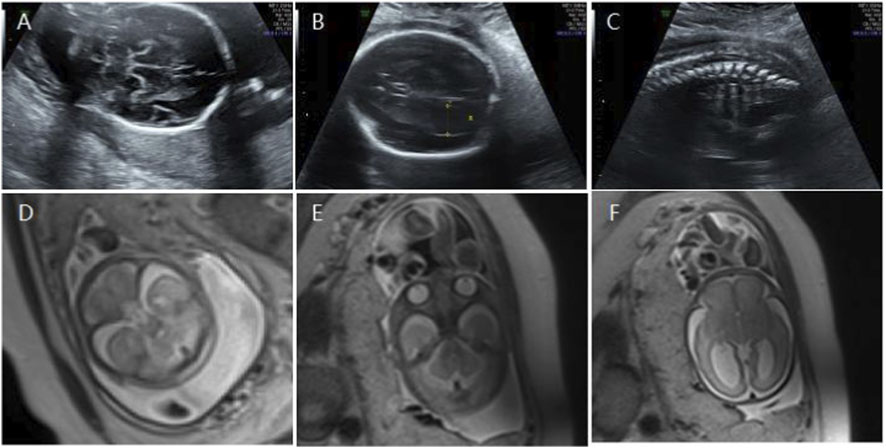

Figure 5

Ultrasound and MRI images labeled A to F. A, B, and C are ultrasound scans displaying different angles of a fetus. A shows a side view, B shows a circular head structure, and C displays the spine. D, E, and F are MRI scans showing axial slices of the fetal brain and body, indicating internal structures and development.

Figure 5. (A) Transverse ultrasound section showing the fetal cerebellum; transverse cerebellar diameter measured 23.4 mm (<–2.6 SD for gestational age). (B) Axial ultrasound view in the transventricular plane demonstrating bilateral ventriculomegaly, with atrial widths of 10.0 mm (left) and 13.6 mm (right). (C) Sagittal ultrasound view showing an abnormally positioned conus medullaris. (D,E) Axial T2-weighted fetal MRI confirming reduced cerebellar size. (F) Axial T2-weighted fetal MRI showing bilateral ventriculomegaly.